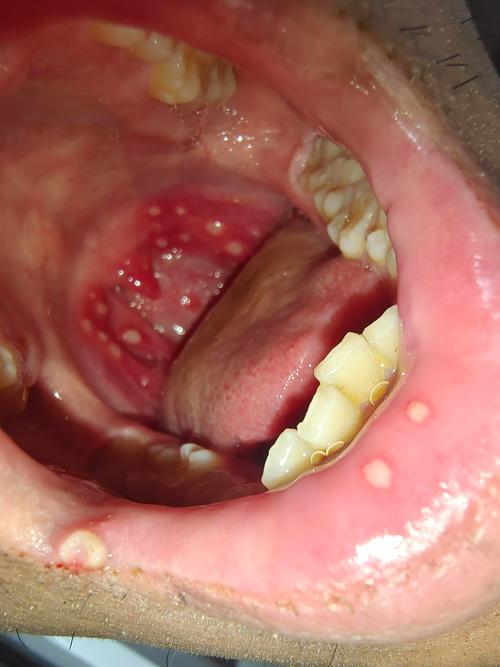

图片3:重型口腔溃疡(软腭)

这是一个发生在软腭的重型口腔溃疡,软腭部位的活动频繁,吞咽动作会直接刺激溃疡,导致疼痛感异常强烈,溃疡面积大,且周围组织充血明显。